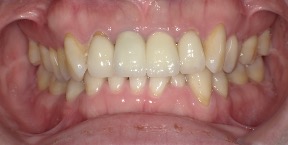

30歳女性のビフォーアフター

| 診断 | 叢生 |

| 治療方針 | 治療方針:インビザラインシステムにて主にIPR(歯と歯の間をわずかに削合してスペースを獲得する方法)を組み込んだ動的矯正治療を行い、叢生を改善後、保定を行う。 |

| 治療費 ※ | 96万5千円(診断、型取り、矯正中のメンテナンス、保定装置を含む料金) |

| 治療期間 | 1年8か月 |

| リスク | 1日20時間以上マウスピースを使用できない場合、歯が動かなかったり、想定しない誤差により不完全に終わる可能性がある。装着時や食事時に痛みを伴う。歯肉退縮や虫歯になるおそれがある。また、指導通りに装着できていない場合や適切なブラッシングが出来ていないとそのリスクが高くなる。歯根が短くなることがある。ごくまれに歯の神経が損傷してしまうことがある。過去にぶつけたり深い虫歯治療をしたことがあるとそのリスクはやや高くなる。矯正後には保定装置が必要。適切な使用ができない場合、後戻りの原因となる。将来的に歯並びが動いて再矯正が必要な場合がある。舌癖(舌で歯を押し出す癖)親知らずが正常に生えていない場合、その可能性がやや高くなる。 |